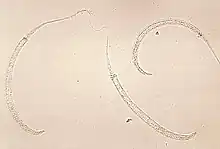

Soil-transmitted helminthiasis is the most prevalent neglected tropical disease.[76] The three major worm species responsible for soil-transmitted helminthiasis are Ascaris (roundworms), Trichuris (whipworm), the hookworms Necator americanus and Ancylostoma duodenale, and Strongyloides stercoralis.[77] There are 1.5 billion people currently infected.[77] Soil-transmitted helminthiasis occurs in sub-Saharan Africa, the Americas, China, and East Asia.[77] The mortality risk is very low.[18] The most common symptoms are anemia, stunted growth, intestinal problems, lack of energy, and compromised physical and cognitive development.[18][77] Infected children often fall behind in schooling.[18] The severity of symptoms depends on the number of worms in the body.[77]

Parasitic worms are generally transmitted via exposure to infected human feces and soil that are spread in the environment, for example, due to open defecation.[77] The most common treatment is medicine.[77] It can be prevented through hygienically prepared food and clean water, improved sanitation, periodic deworming, and health education.[77] The World Health Organization recommends mass deworming without prior diagnosis.[77]